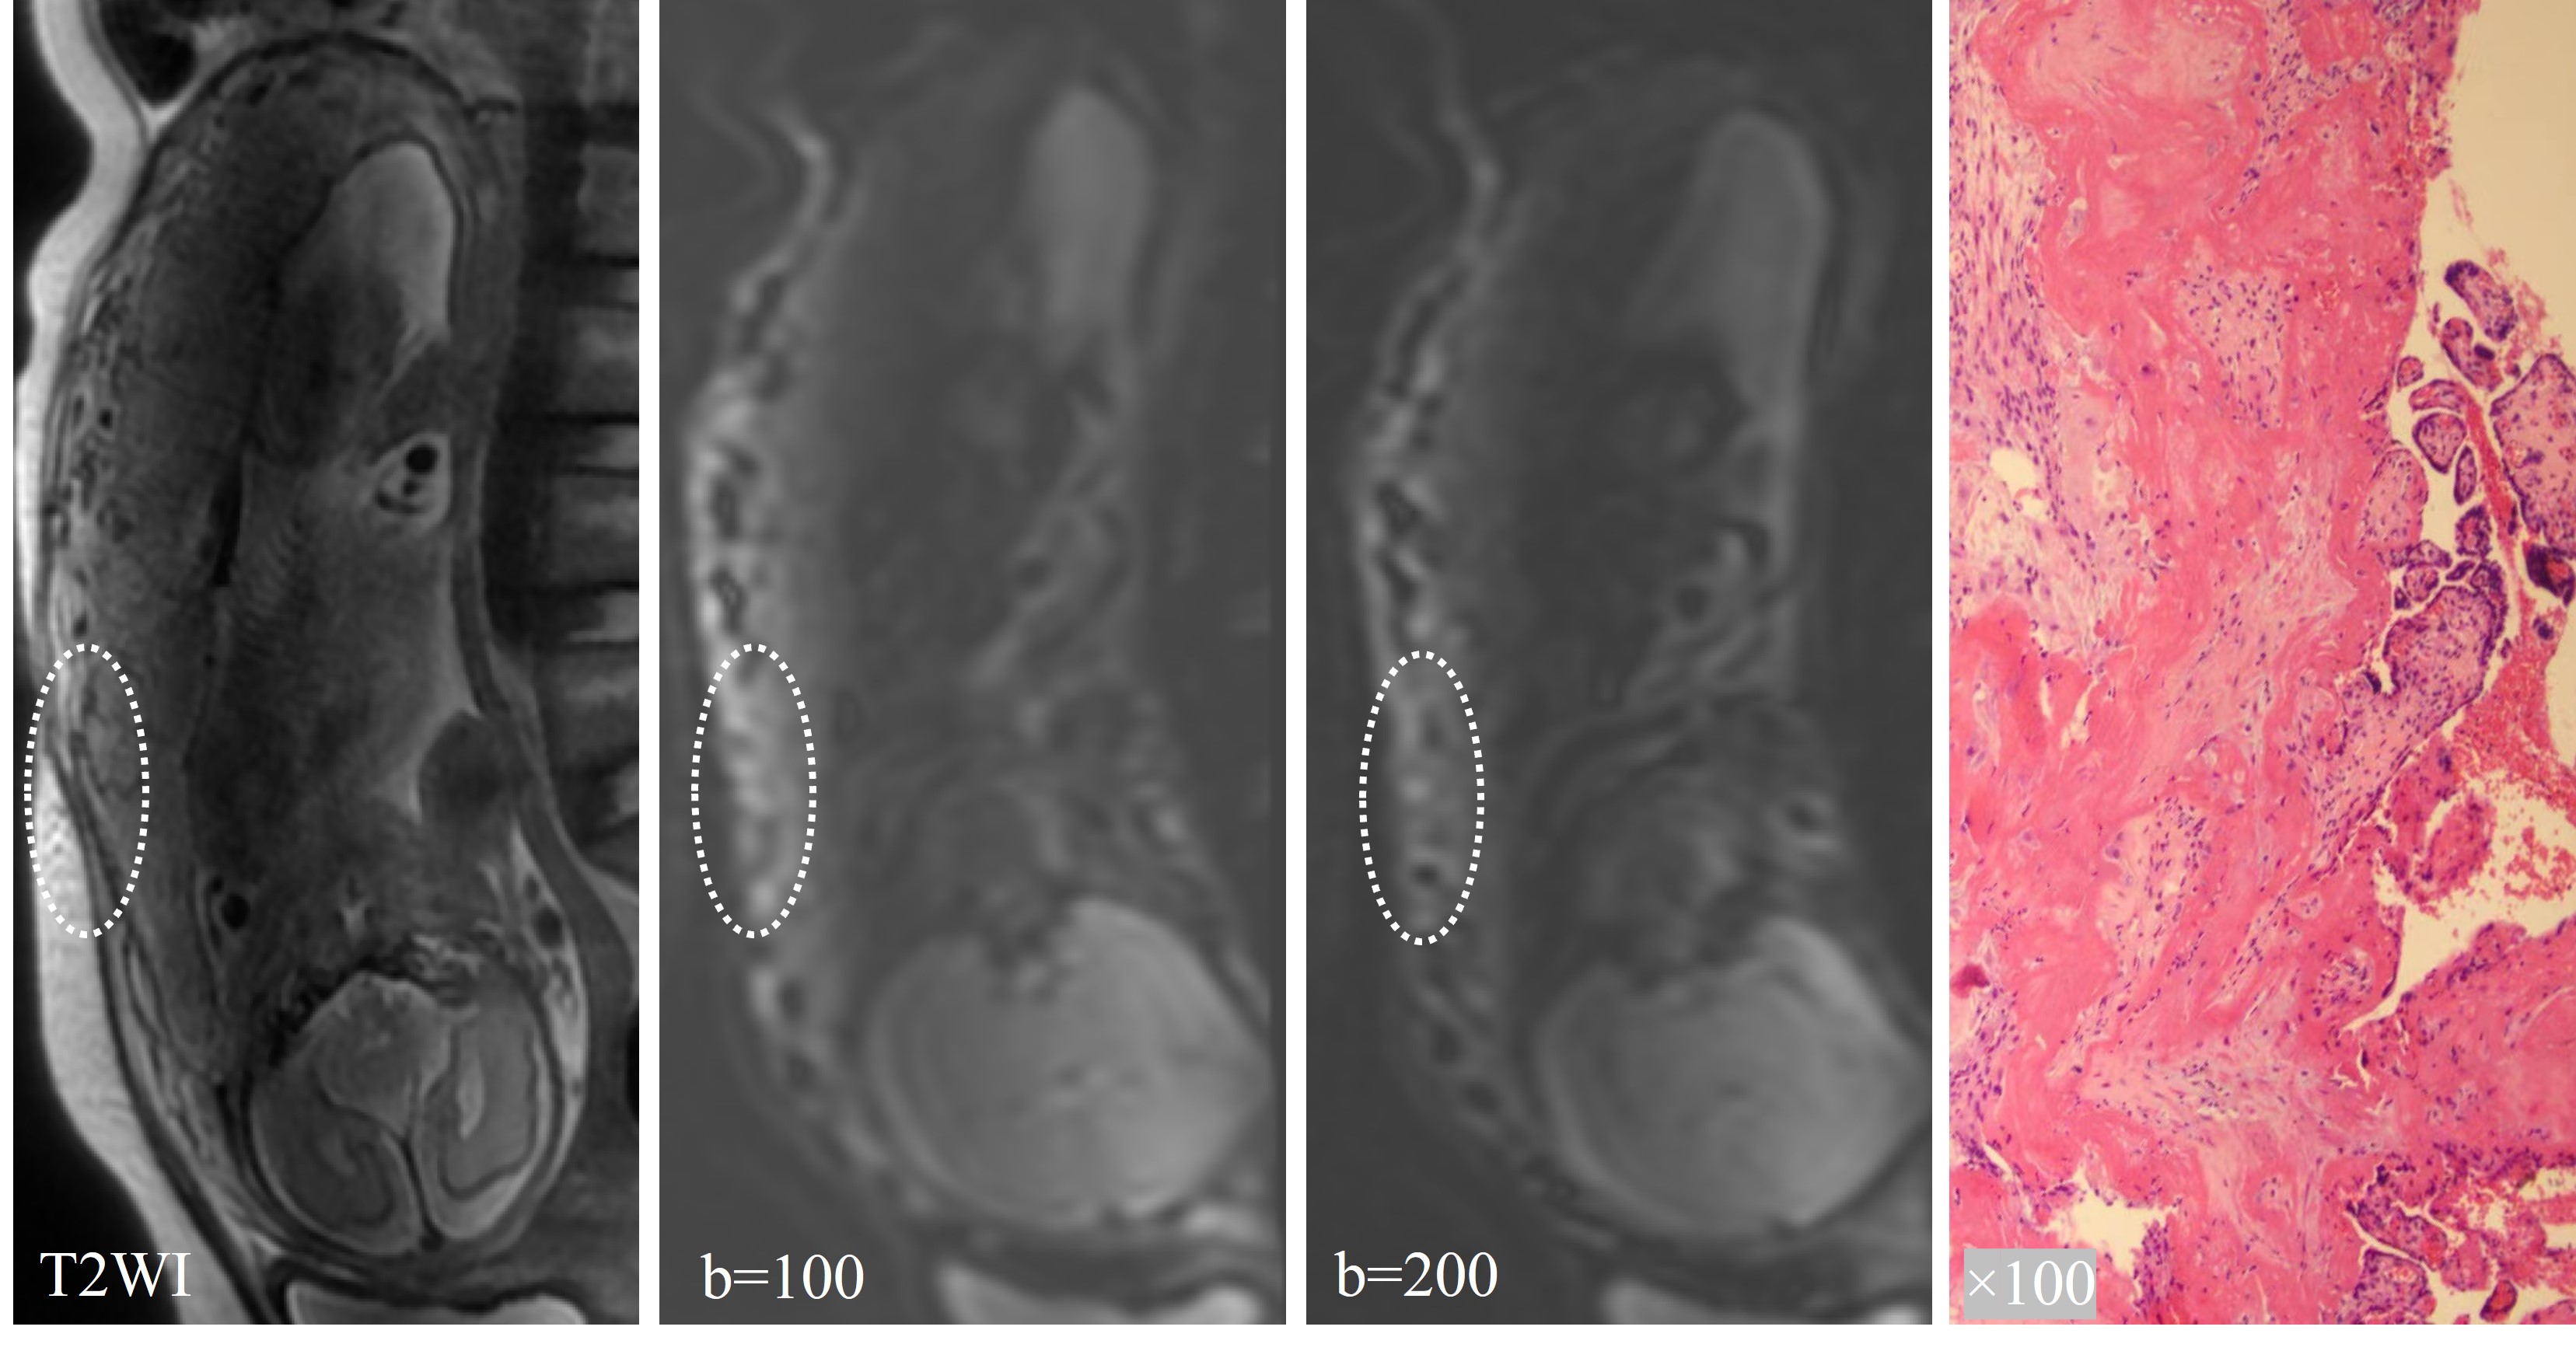

Figure 3 demonstrated three-layer structure of the placenta according to the images of pathologic tissue section. The original IVIM images clearly showed the outer myometrium as a strip of slightly high signal. There was a strip of low signal under the myometrium corresponding to the placental basal plate in the pathologic tissue section. The original IVIM image can more clearly show the myometrium as a strip of slightly high signal shadow, with a strip of low signal shadow under the myometrium corresponding to the basal layer of the placenta in the pathological section. Several short discontinuities (<10 mm in length) were seen in the low signal band of the basal layer, which was considered to be probably related to the curvature of the fibrous tissue of the basal layer (Figure 3C). The inner part of the basal plate was placental villous portion.

Figure 3. The three-layer structure of the placenta according to the images of pathologic tissue section. The large arrow showed the myometrium and the small arrow indicated placental basal plate. Black stars refered to the fibrous tissue in the placental basal plate.